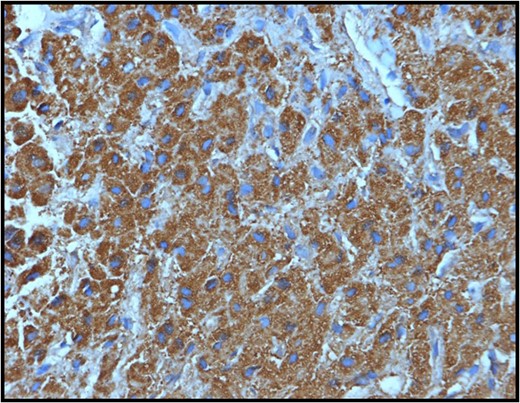

Section from the hepatic mass showing positive staining of the tumor cells with the hepar IHC stain confirming the hepatic nature of the liver mass.